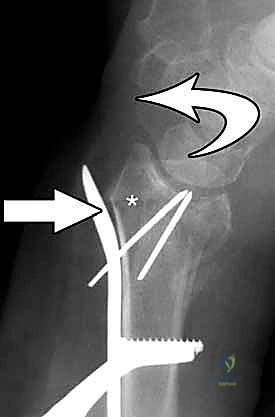

3. إرجاع الكسر (Fracture Reduction)

تُعد هذه الخطوة الأهم. باستخدام أدوات دقيقة وجهاز الأشعة السينية المباشر في غرفة العمليات (C-arm fluoroscopy)، يقوم الدكتور هطيف بإعادة ترتيب شظايا العظام إلى مكانها التشريحي الأصلي، مع التركيز الشديد على استواء السطح المفصلي.

4. وضع الصفيحة والتثبيت المؤقت

يتم اختيار صفيحة تيتانيوم مصممة تشريحياً لتلائم انحناء الكعبرة. توضع الصفيحة على العظم وتُثبت مؤقتاً بأسلاك معدنية دقيقة (K-wires).